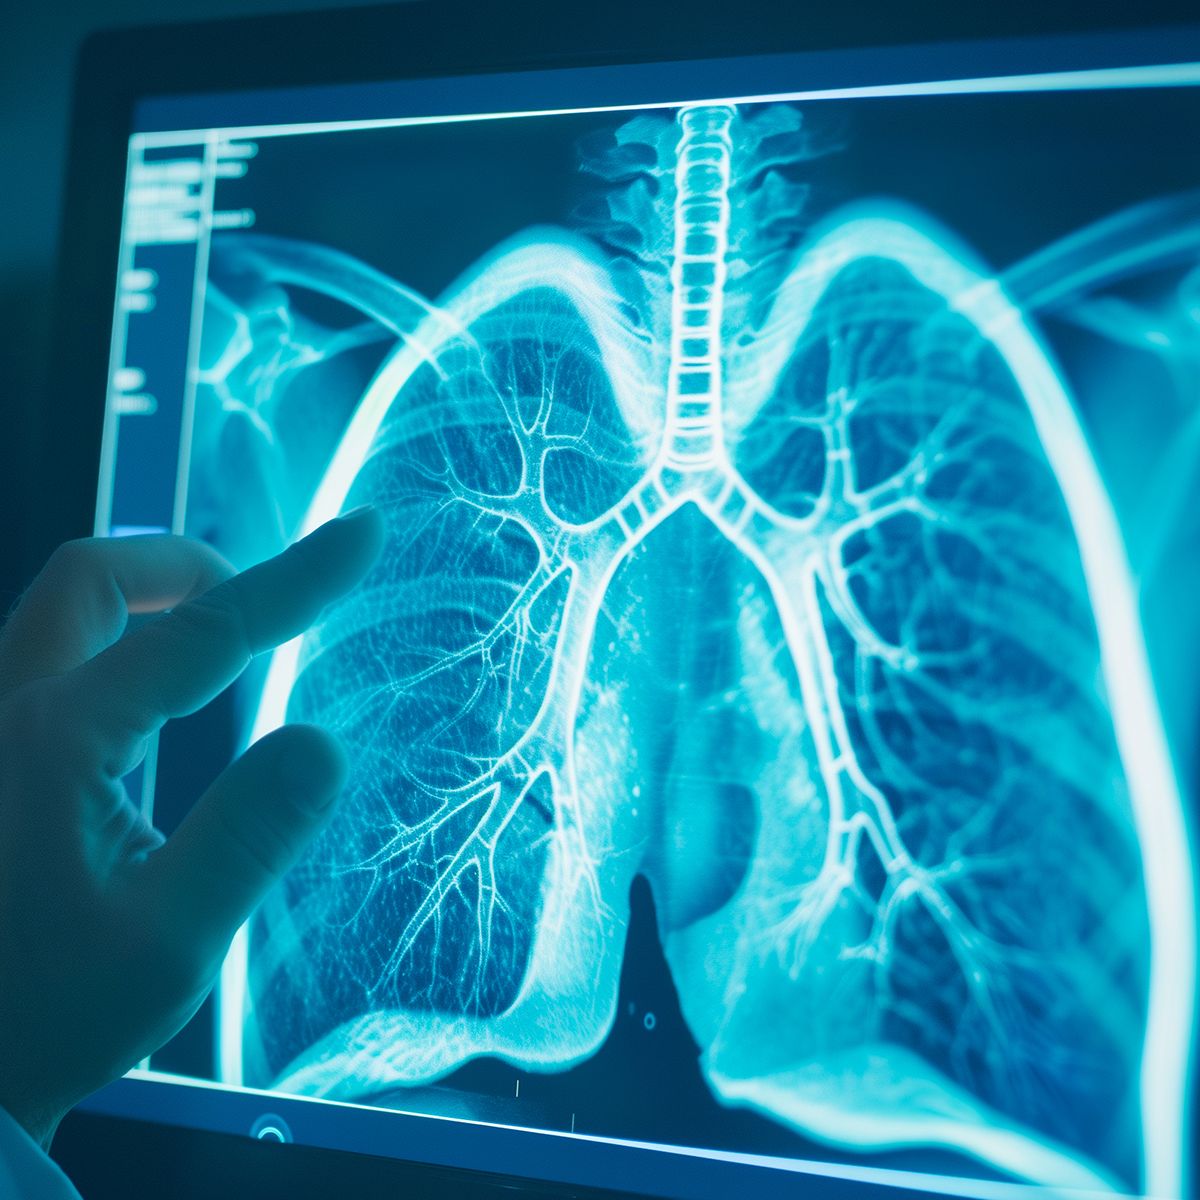

Correctly distinguishing between correlation and causation is critical because it influences how treatments for illnesses are devised and tested. Also, in the context of the law, it ensures that as the wheels of justice turn, reputations, lives and …